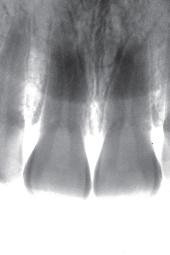

An orthopantomogram (OPG) revealed RL8 and LL8 were mesioangularly impacted and their roots were crossing both upper and lower white lines of the inferior alveolar canal (IAC). LL8 roots showed darkening of root at the level of IAC (Fig 1).

LL8: IAC was running buccal to roots of LL8 which had 3 roots (Fig 2).